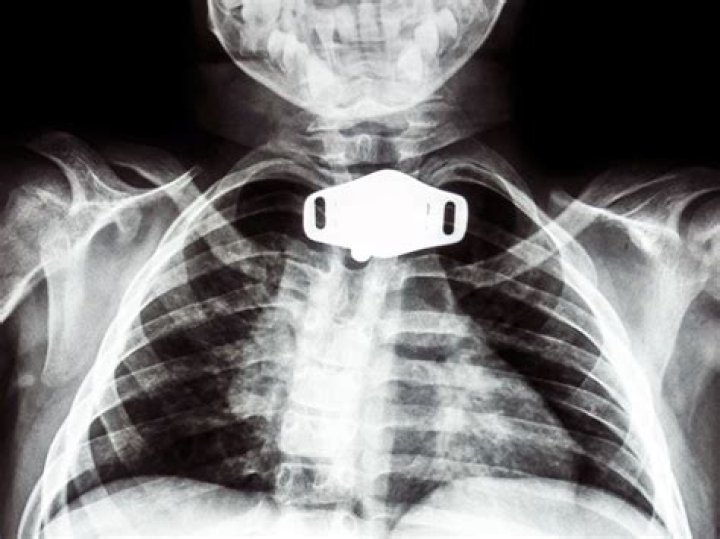

A tracheostomy is an opening created at the front of the neck so a tube can be inserted into the windpipe (trachea) to help you breathe. If necessary, the tube can be connected to an oxygen supply and a breathing machine called a ventilator.

A tracheostomy is usually done for one of three reasons: to bypass an obstructed upper airway; to clean and remove secretions from the airway; to more easily, and usually more safely, deliver oxygen to the lungs.